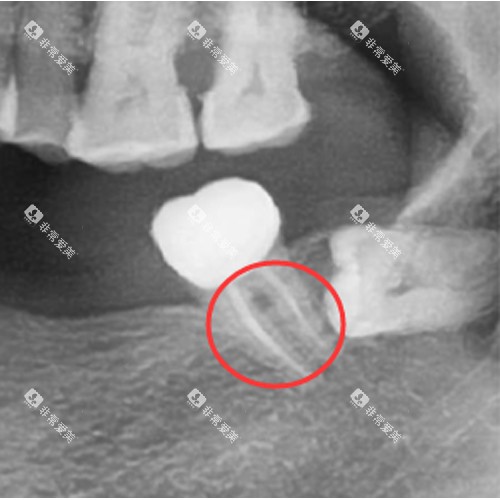

例如智能化口腔扫描仪,能够快速、较准地获取患者牙齿的模型,让患者提前直观看到治疗后的改善;还有口腔CT等设备,为医生提供更完善、清晰的口腔影像,有助于制定精细的治疗方案。